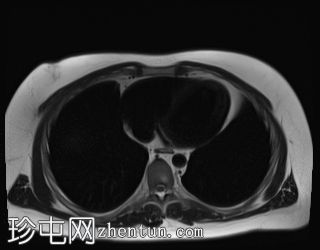

轴位T2加权像

脂肪抑制序列

T1低信号,T2低信号为主的脾脏肿块,内部可见T2高信号分隔,呈进行性强化。肿块中央可见星状瘢痕。

脾脏硬化性血管瘤样结节性转化(SANT),9.8 cm肿块

顾名思义,脾脏硬化性血管瘤样结节性转化(SANT)是一种纤维性血管病变。本病例展示了SANT的一些典型影像学特征,包括边界清晰的病灶,中央可见瘢痕,以及呈放射状进行性强化。这些特征使得术前MRI诊断较为明确。尽管SANT是一种良性病变,但大多数患者仍需行脾切除术以明确病理诊断。